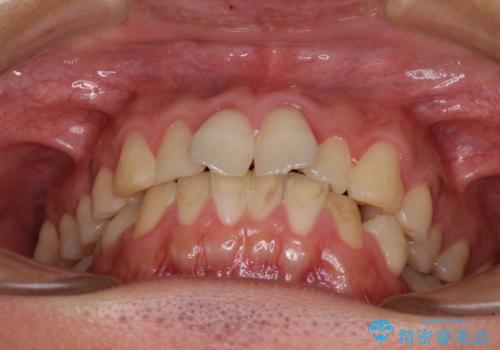

- 上下前歯のデコボコと、それに伴う出っ歯を気にして来院された患者様です。

インビザラインによる上下歯列の側方拡大と後方移動、IPR(歯と歯の間を削る)にるスペースの獲得により歯列を整えることとしました。